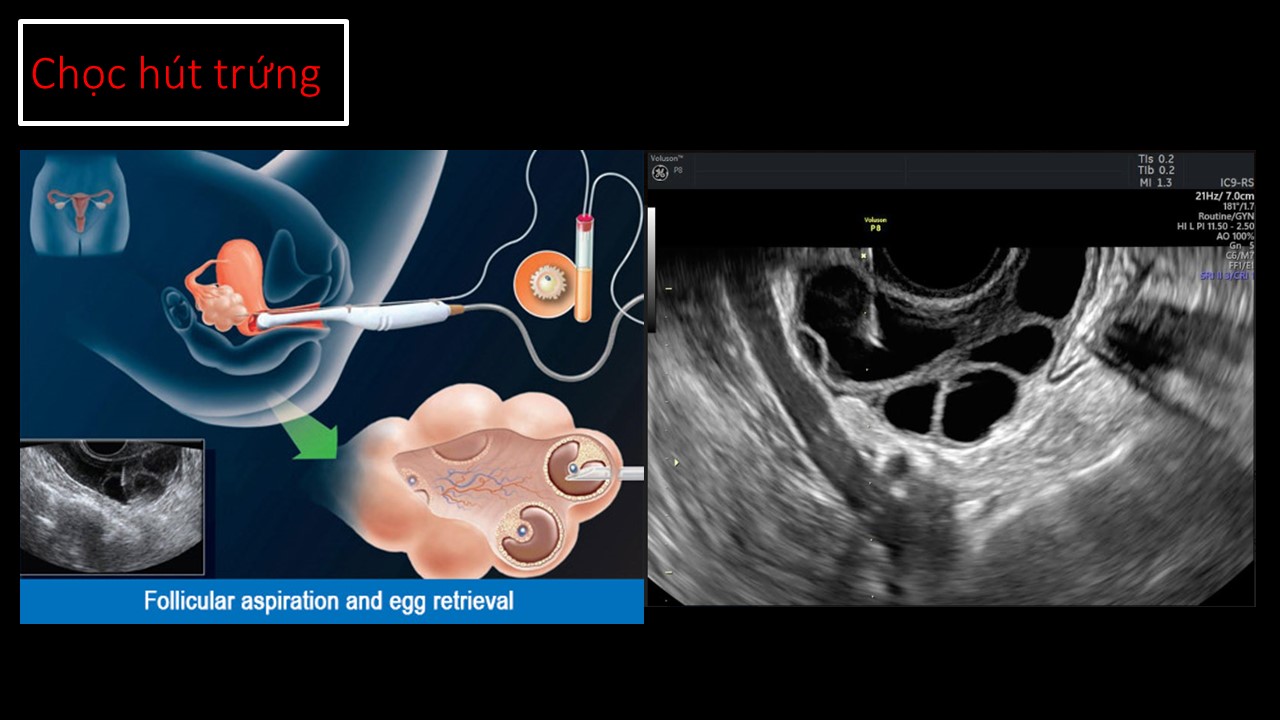

Vai trò của siêu âm trong chẩn đoán và điều trị hiếm muộn

Từ khóa: Vai trò của siêu âm trong chẩn đoán và điều trị hiếm muộn